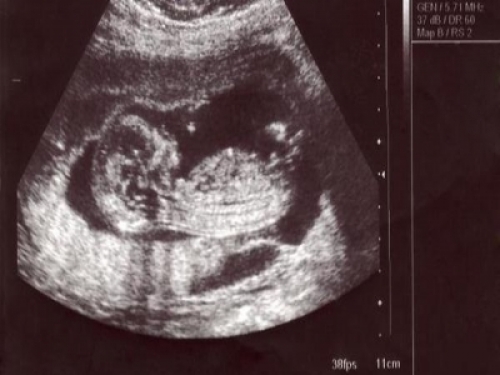

經過辛苦的十個月的等待,小寶寶終於出生了。孕期忌口,這也不能吃那也不能吃,卸完貨有的寶媽迫不及待的想大吃特吃,把這十個月不能吃的統統補回來。

產婦在月子裡吃飯各方面都要講究,不能由著自己的性子來。就算嘴再饞,這四種食物再怎麼想吃,也要忍住了,千萬不要吃。